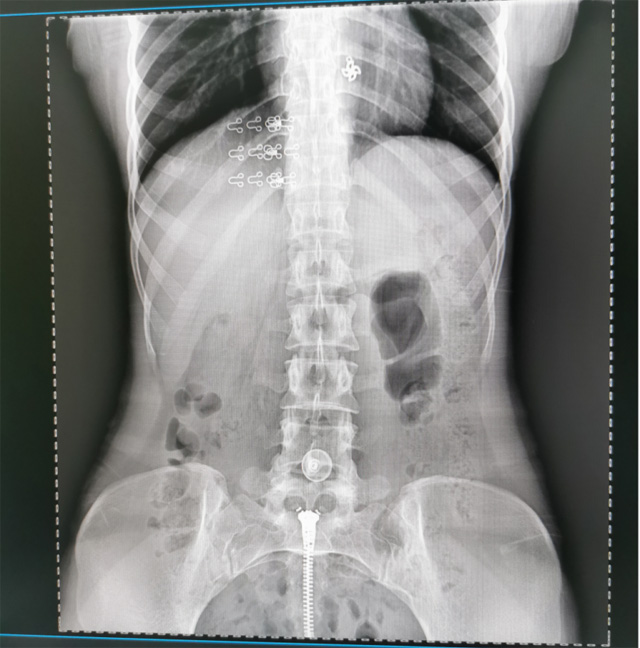

懸吊DR數(shù)字化攝影圖像質(zhì)量高輻射量少誤差小滿足疾病的臨床診斷

提高醫(yī)院的影像科的醫(yī)療服務(wù)水平,滿足滿足人民群眾不斷增長的醫(yī)療需求,促進醫(yī)療技術(shù)快速發(fā)展。醫(yī)院都引進懸吊DR拍片設(shè)備新一代數(shù)字化X線攝影系統(tǒng)。標(biāo)志著醫(yī)院的診療水平又上升一個新的臺階。懸吊DR滿足人體頭部、胸部、腹部、腰椎、四肢等部位的數(shù)字攝影檢查,可以檢查呼吸系統(tǒng)疾病,心臟系統(tǒng)的疾病、骨關(guān)節(jié)系統(tǒng)的疾病,子宮輸卵管造影、胃腸道造影,.有職業(yè)病體檢篩查塵肺病功能。通過DR數(shù)字化攝影,分段連續(xù)、重疊采集數(shù)字化圖像,利用軟件對圖像進行拼接的方式來獲得全脊柱、全上肢或全下肢的圖像。新設(shè)備的圖像更清晰,臨床拍攝避免患者再次搬運和移動產(chǎn)生的痛苦,是創(chuàng)傷骨折患者的福音。輻射減少受照劑量50%,后處理能力強、圖像質(zhì)量高。有效降低操作難度,縮短工作流程,尤其適合大批量體檢。

具有射線劑量小、圖像清晰度高、誤差小等特點,懸吊DR已廣泛應(yīng)用于各級醫(yī)療機構(gòu)的體檢中心,越來越受到臨床醫(yī)生的肯定和患者的青睞。為臨床診斷工作提供更加直觀有效的技術(shù)支持,大大提高了患者就醫(yī)效率從而為患者提供更加優(yōu)質(zhì)的醫(yī)療服務(wù)。提高了其成像質(zhì)量和臨床應(yīng)用價值,并極大減少了受照輻射劑量。有效滿足了各種常見疾病的臨床診斷和治療需求。以醫(yī)療質(zhì)量為根本,以優(yōu)質(zhì)服務(wù)為導(dǎo)向,竭誠為人民群眾的健康保駕護航。